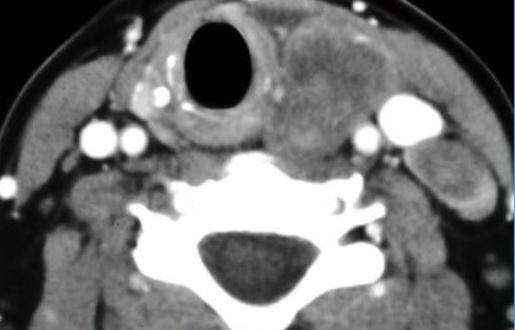

Компьютерная томограмма щитовидной железы

По компьютерным сканограммам специалист может судить о форме, размерах, строении и положении органа, состоянии лимфоузлов, паращитовидных желез, трахеи, пищевода, наличии или отсутствии патологических изменений.

Опухоль щитовидной железы на компьютерной томографии

Фото КТ щитовидной железы с контрастом

Узловой зоб щитовидной железы на компьютерной томограмме (очаговые изменения указаны стрелками)

На снимке КТ белой стрелкой указан увеличенный лимфатический узел. У пациента удалена доля щитовидной железы справа (указано чёрной стрелкой), в связи с папиллярной карциномой.

В норме поперечные томограммы щитовидной железы показывают две однородные по структуре доли, прилегающие к трахее. Между ними узкий перешеек, рядом визуализируются мышцы, нервные и сосудистые пучки. Когда присутствуют опухоли, кисты, узловые образования, симметричность долей нарушается, строение органа становится гетерогенным (неоднородным).